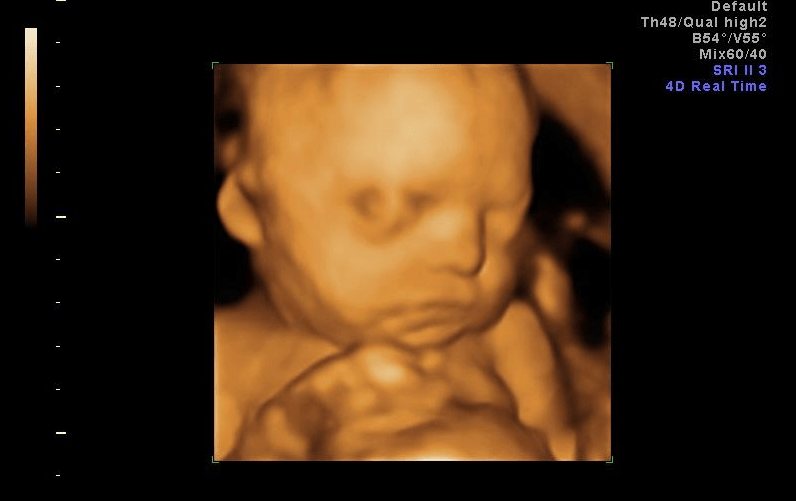

aborto